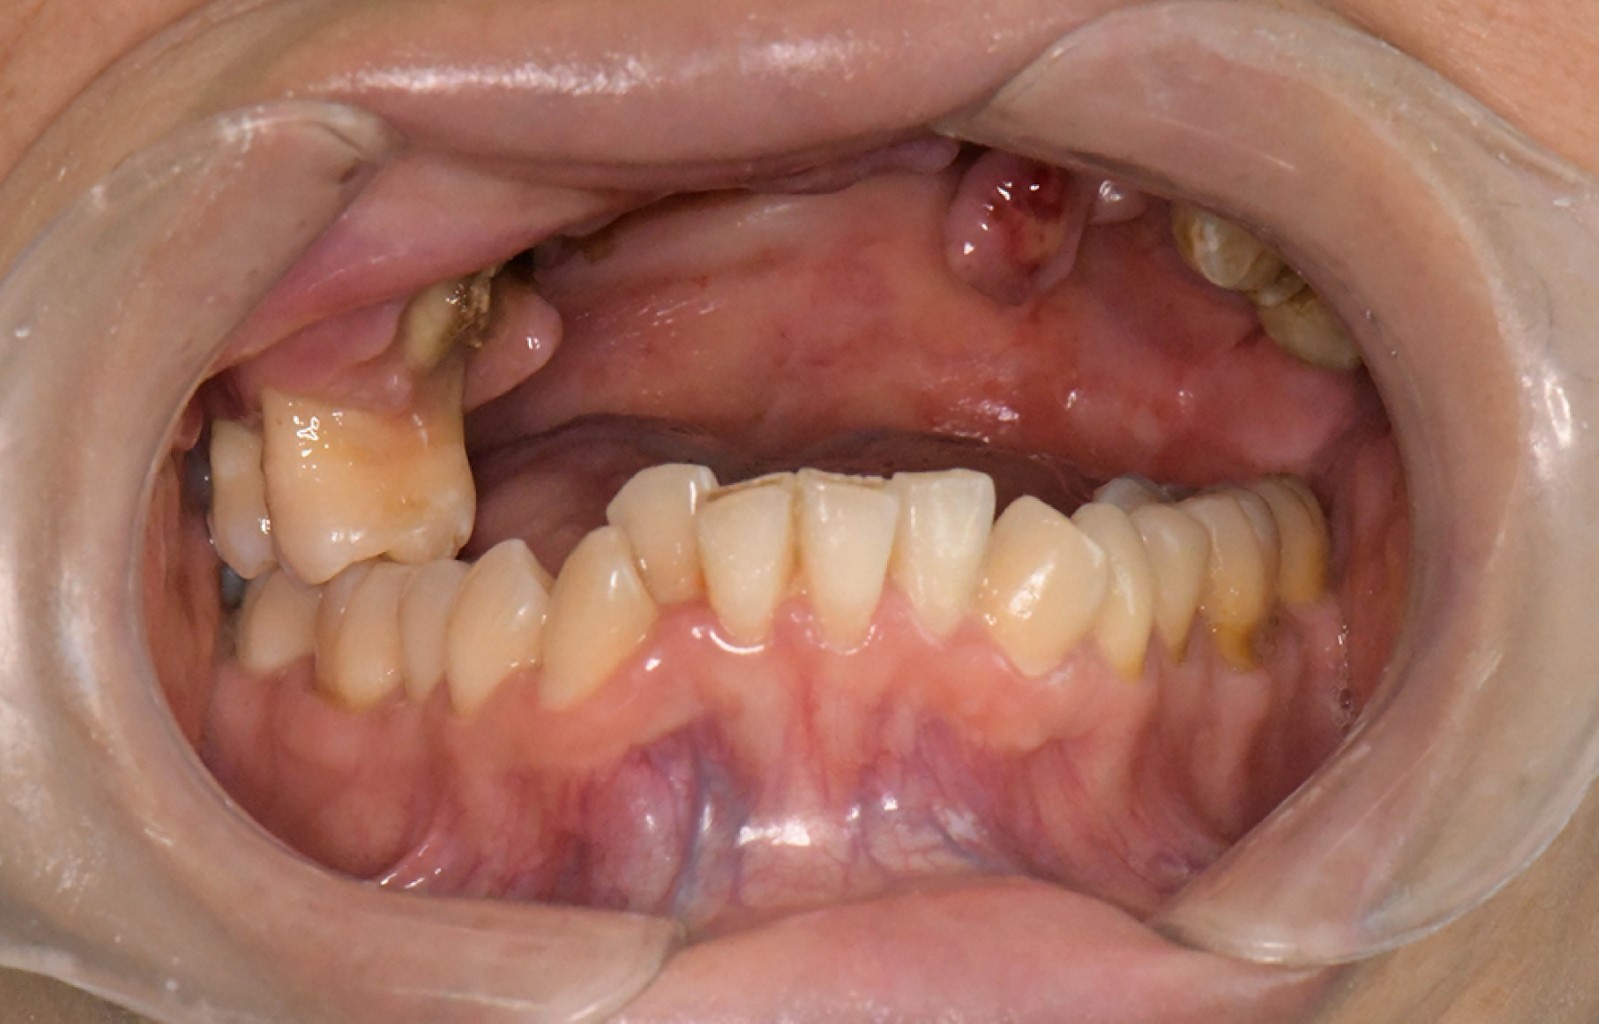

Durante el seguimiento, en 2021 el paciente refirió aumento de volumen en la región malar izquierda, asociado a molestias en el tercer molar superior derecho (Figura 1). En 2023, se documentaron signos clínicos compatibles con osteorradionecrosis maxilar, con evidencia de necrosis ósea. Se indicó la realización de una biopsia, en la cual se identificó infección por Actinomyces (Figura 2). Posteriormente se observó progresión de la lesión en el sitio de la biopsia, con evidencia de comunicación hacia el piso de la cavidad nasal, movilidad dentaria y dolor persistente. El abordaje terapéutico incluyó manejo antibiótico y administración del esquema PENTOCLO (pentoxifilina + tocoferol).

Figura 1

Figura 2